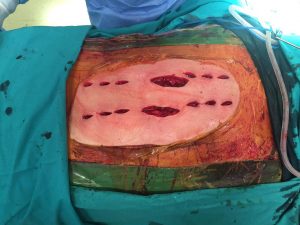

Η χειρουργική επέμβαση πραγματοποιήθηκε τον Δεκέμβριο. Η σταθεροποίηση της Θωρακικής Μοίρας της Σπονδυλικής Στήλης (Θ.Μ.Σ.Σ.) δια της διαδερμικής εφαρμογής συστήματος σπονδυλοδεσίας, κατόπιν οπισθίας προσπελάσεως.

Η χειρουργική επέμβαση έγινε υπό συνεχή νευροπαρακολούθηση και η διαδερμική τοποθέτηση των κοχλιών στους σπονδύλους έγινε με το σύστημα πλοήγησης O-ARM.

- δ

Εικόνα 3 Διεγχειρητικές φωτογραφίες .Τοποθέτηση των κοχλιών στα σπονδυλικά σώματα: Οι κοχλίες είναι ειδικοί αυλοφόροι που παρέχουν τη δυνατότητα να εγχέεται methylmethacrylate (ακρυλικό τσιμέντο) μέσα στα σπονδυλικά σώματα, για ασφαλέστερη συγκρότηση των κοχλίων. Οι ράβδοι τοποθετούνται επίσης διαδερμικά.

-3. Η σταθεροποίηση του κατάγματος της Θωρακικής Μοίρας της Σπονδυλικής Στήλης (Θ.Μ.Σ.Σ), πραγματοποιήθηκε με την εφαρμογή συστήματος σπονδυλοδεσίας, το οποίο τοποθετήθηκε διαδερμικά. Με την τεχνική αυτή περιορίζονται σημαντικά οι κακώσεις των μαλακών μορίων και οι απώλειες αίματος, γεγονός που σημαίνει οτι η κινητοποίηση του χειρουργημένου είναι πολύ γρήγορη.

Δεδομένου ότι οι κοχλίες τοποθετούνται μέσα στα σπονδυλικά σώματα, υπό την καθοδήγηση του ειδικού ακτινολογικού συστήματος πλοήγησης O-ARM εξασφαλίζεται η, με μεγίστη ασφάλεια, είσοδος των κοχλίων σε περιοχές εξαιρετικά επικίνδυνες λόγω της ύπαρξης νευρικών και αγγειακών στοιχείων (8).

Δια της εφαρμοζόμενης διαδερμικής τεχνικής στη τοποθέτηση των υλικών σπονδυλοδεσίας επίσης περιορίζονται σημαντικότατα οι κίνδυνοι να προκληθούν νεκρώσεις του δέρματος και λοιμώξεις, λόγω των προηγηθεισών ακτινοβολιών στη περιοχή αυτή της Σπονδυλικής Στήλης.